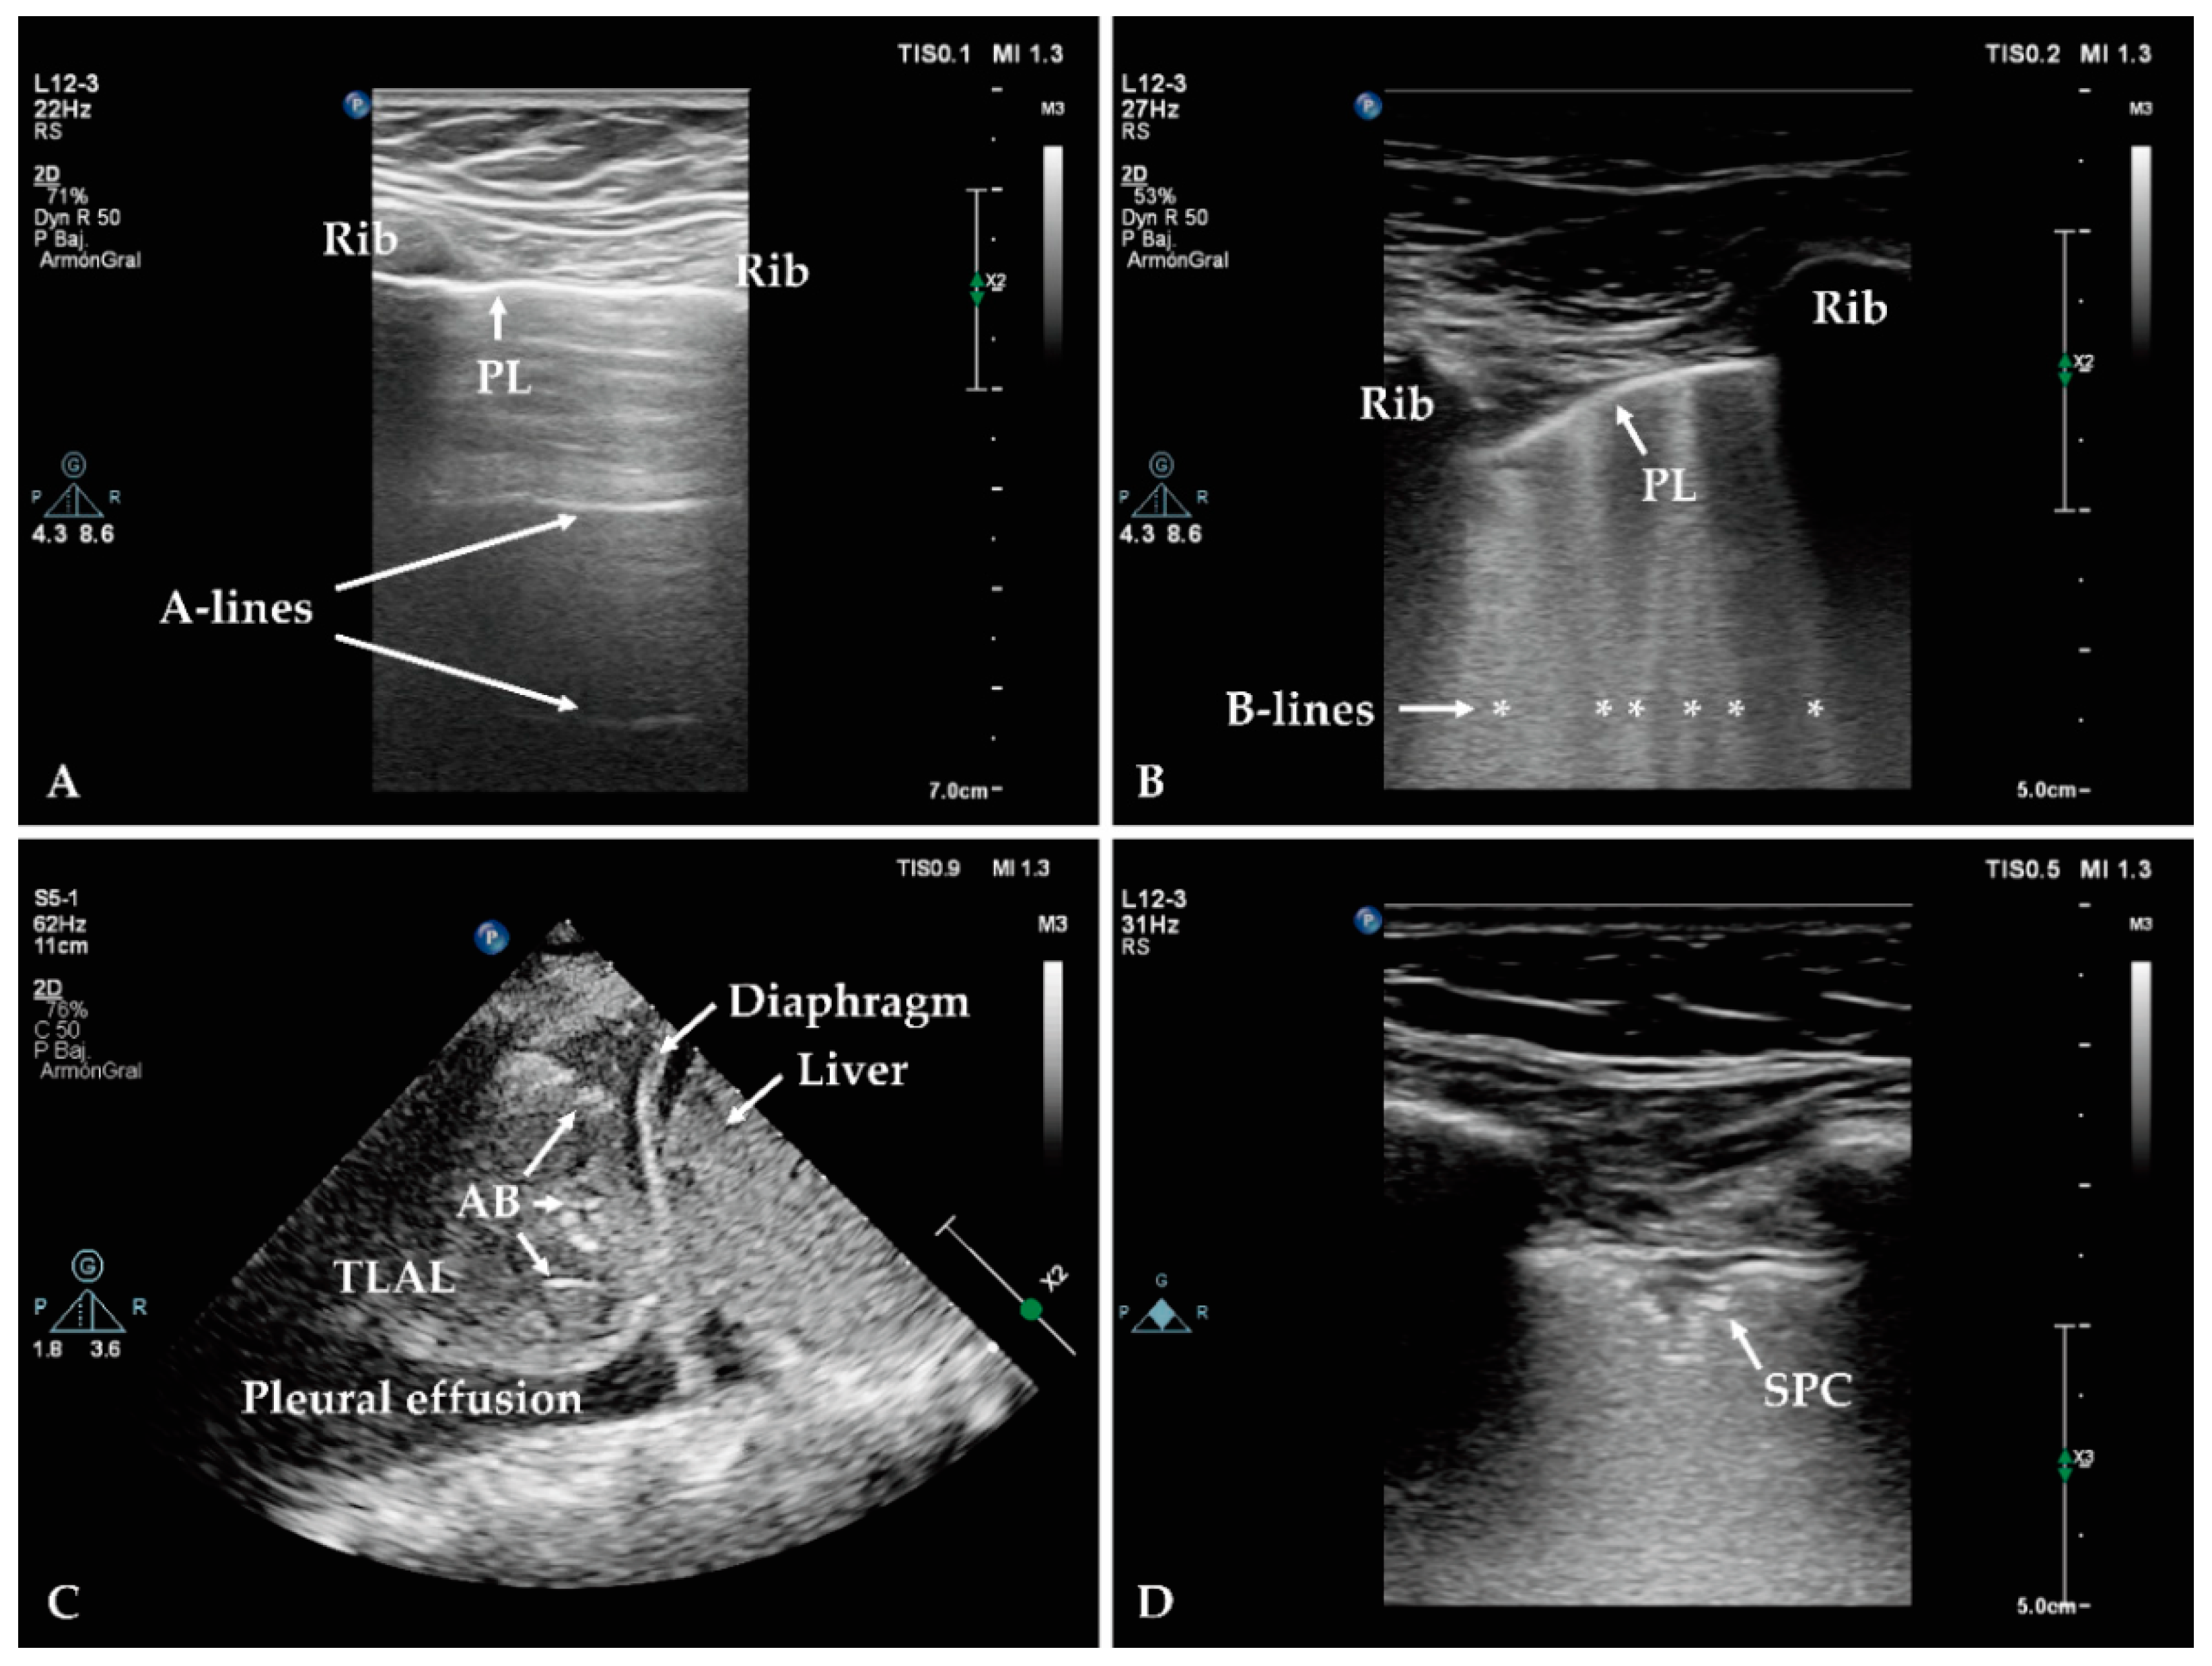

- Hoesein, F.M. Low-dose computed tomography instead of radiography in suspected pneumonia. Breathe 2019, 15, 81–83. [Google Scholar] [CrossRef]

- Prendki, V.; Scheffler, M.; Huttner, B.; Garin, N.; Herrmann, F.; Janssens, J.-P.; Marti, C.; Carballo, S.; Roux, X.; Serratrice, C. Low-dose computed tomography for the diagnosis of pneumonia in elderly patients: A prospective, interventional cohort study. Eur. Respir. J. 2018, 51, 1702375. [Google Scholar] [CrossRef]

- Kroft, L.J.; van der Velden, L.; Girón, I.H.; Roelofs, J.J.; de Roos, A.; Geleijns, J. Added value of ultra-low-dose computed tomography, dose Equivalent to chest x-ray radiography, for diagnosing chest pathology. J. Thorac. Imaging 2019, 34, 179. [Google Scholar] [CrossRef] [PubMed]